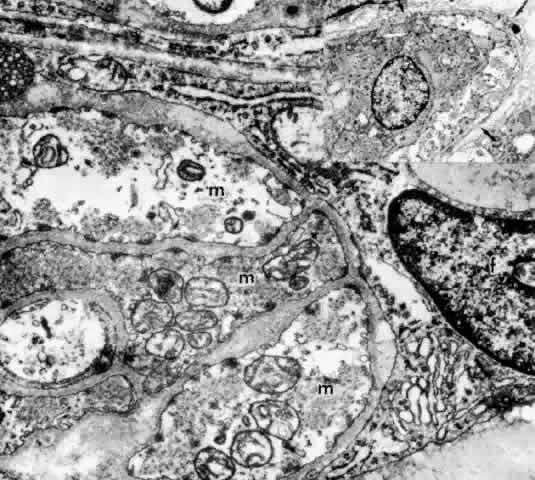

The ultrastructure of the ciliary muscle fibers resembles that of smooth muscle elsewhere, with a few interesting differences. The muscle bundles are surrounded by a sheath of flattened fibrocytes rather than primarily by collagen fibers (Fig. 37),46–48 showing that they belong to the multiunit family of smooth muscles instead of the syncytial family.49 Each fiber is covered by a continuous basement membrane and has many pinocytotic vesicles or caveolae on the plasmalemmal membrane. The fiber is filled with 60- to 70-nm myofibrils that show the usual attachment densities among them, as well as focally where they attach to the basement membranes (Fig. 38). These myofibrils are the intermediate filaments of the cell and contain the protein desmin, used to identify smooth or skeletal muscle cells by immunohistochemistry. A less specific protein, smooth muscle actin, is also present but characterizes myofibroblasts as well. Mitochondria and endoplasmic reticulum are more numerous and Golgi apparatus better developed than in most smooth muscle cells. Occasional desmosomes interconnect the cells but no gap junctions. Studies of muscle enzymes have suggested that there may be functional differences between the longitudinal muscle and the radial-circular muscle complex.50 The longitudinal muscle cells, particularly their anterior tips, are heavily fibrillar with fewer mitochondria than the other muscles and have enzyme characteristics somewhat like those of skeletal rapid twitch fibers. It is hypothesized that their multiunit structure might allow the muscle tips to react first in accommodation, stiffening them to counteract the posterior pull of the remaining muscle on the scleral spur.

Fig. 37. Inset. Thin fingers of fibrocyte cytoplasm (arrows) surround a bundle of ciliary muscle fibers. Main figure. Three muscle fibers (m) surrounded by processes of a fibrocyte (f). Thick basement membrane around each muscle fiber and several nerve terminals are visible. (X 33,800; Inset, X 8500)